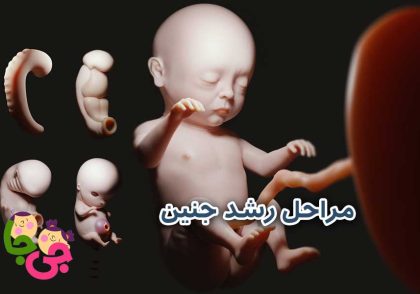

هفته ۲۱ تا ۲۴ بارداری

بین هفته ۲۱ تا ۲۴ بارداری، جنین وارد مرحلهای بسیار حساس و پرشتاب از رشد میشود. در این بازه، سرعت افزایش وزن و طول بدن بیشتر از قبل است و اندامهای حیاتی بهتدریج به سمت تکامل پیش میروند. جنین شروع به شکلگیری الگوی خواب و بیداری میکند؛ به این معنا که دورههایی از فعالیت و آرامش دارد که ممکن است با ریتم بدن مادر هماهنگ نباشد. این حرکات و تغییرات نشاندهندهی رشد سیستم عصبی و ارتباط بهتر بین مغز و عضلات هستند.

پوست جنین که تا پیش از این نازک و شفاف بوده، کمکم ضخیمتر میشود و با لایهای از چربی محافظ (ورنیکس) و موهای نرم و کرکی (لانگو) پوشیده میگردد تا از او در برابر محیط مایع رحم محافظت کند. ریهها هنوز کامل نیستند، اما حرکات تنفسی تمرینی آغاز میشود و این تمرینها زمینهساز توانایی تنفس پس از تولد خواهند بود. در این مرحله، اگرچه احتمال زندهماندن نوزاد در صورت تولد زودرس وجود دارد، اما همچنان بسیار پایین است و با خطر بالای نارساییهای شدید و مشکلات رشدی یا معلولیت همراه خواهد بود.